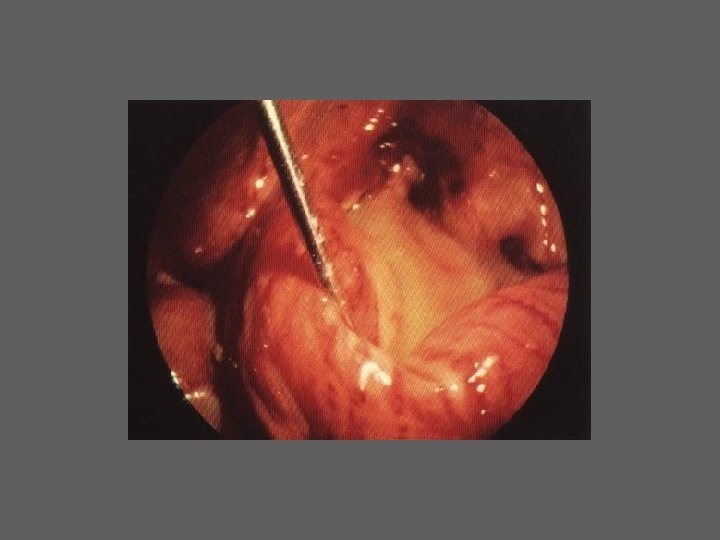

HISTEROSCOPIA - INDICAÇÕES Todas a situações em que se julgue vantajosa uma visualização completa da cavidade uterina, em particular: – Metrorragias – Dismenorreia adquirida – Infertilidade – Abortamentos de repetição e parto pré-termo – HSG anormal – DIU “perdido” – GIFT e ZIFT – Tratamento cirúrgico da patologia intracavitária: ● pólipos, miomas, septos, sinéquias, recessões endometriais ● baixos custos, reduzida morbilidade

HISTEROSCOPIA - MATERIAL CO 2 – Insuflador – Metrorragias max. 100 ml /min p < 100 mm Hg liquido (soro glicosado, dextrano, etc. ) – Fonte de luz fria – Histeroscópio (3, 5, 7 mm) – rígido ou flexível – Bainha e instrumentos cirúrgicos (pinça de biopsia, tesoura, etc.